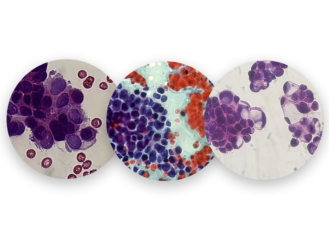

Nuestros Estudios

En H&E Diagnostics contamos con tecnología de última generación y personal altamente capacitado para el diagnóstico y entrega oportuna de resultados ofreciendo los siguientes servicios especializados: